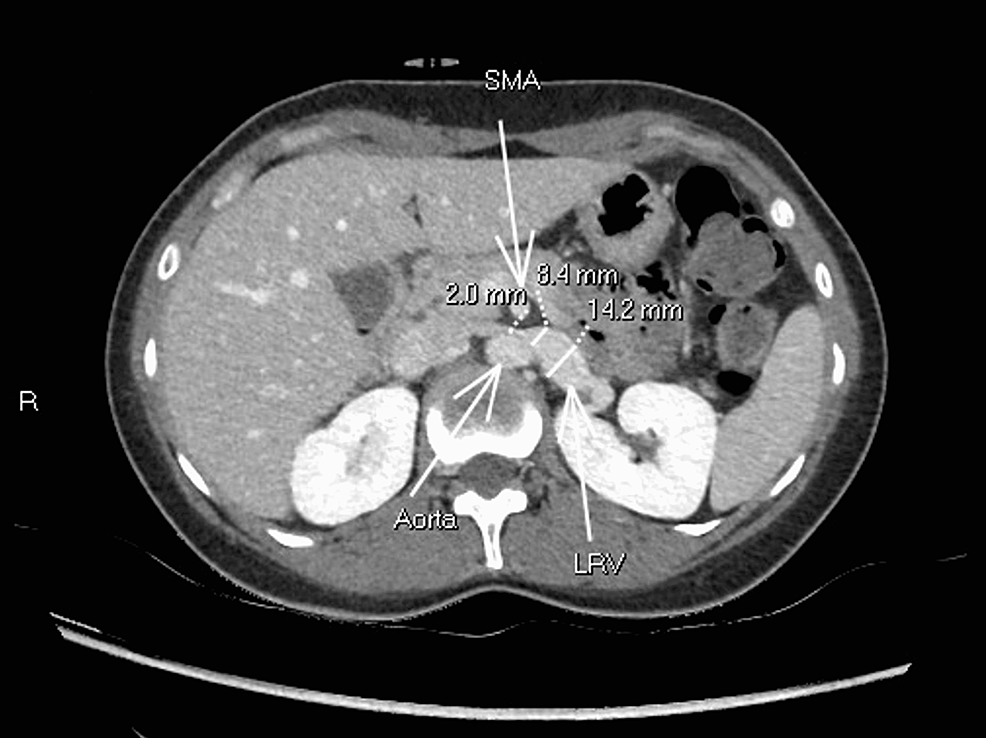

Abdominal MRA images of a patient with nutcracker syndrome. a) axial

Abdominal MRA images of a patient with nutcracker syndrome. a) axial Nutcracker Syndrome Abdominal Pain Entrapment of the left renal vein between superior mesenteric artery and aorta is known as nutcracker phenomena, while. Nutcracker syndrome (ncs), a rare but impactful vascular condition, emerges from the compression of the left renal vein by adjacent. Nutcracker syndrome (ncs) is an extrinsic compression of the left renal vein (lrv) by the superior mesenteric artery (sma). The most common. Nutcracker Syndrome Abdominal Pain.